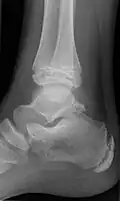

Accessory navicular

An accessory navicular bone, also called os tibiale externum, occasionally develops in front of the ankle towards the inside of the foot. This bone may be present in approximately 2–21% of the general population and is usually asymptomatic.[18][19][20] When it is symptomatic, surgery may be necessary.

The Geist classification divides the accessory navicular bones into three types.[20]

- Type 1: An os tibiale externum is a 2–3 mm sesamoid bone in the distal posterior tibialis tendon. Usually asymptomatic.

- Type 2: Triangular or heart-shaped ossicle measuring up to 12 mm, which represents a secondary ossification center connected to the navicular tuberosity by a 1–2 mm layer of fibrocartilage or hyaline cartilage. Portions of the posterior tibialis tendon sometimes insert onto the accessory ossicle, which can cause dysfunction, and therefore, symptoms.

- Type 3: A cornuate navicular bone represents an enlarged navicular tuberosity, which may represent a fused Type 2 accessory bone. Occasionally symptomatic due to bunion formation.